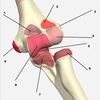

1

Not at all

2

3

4

5

Perfectly

14

Q